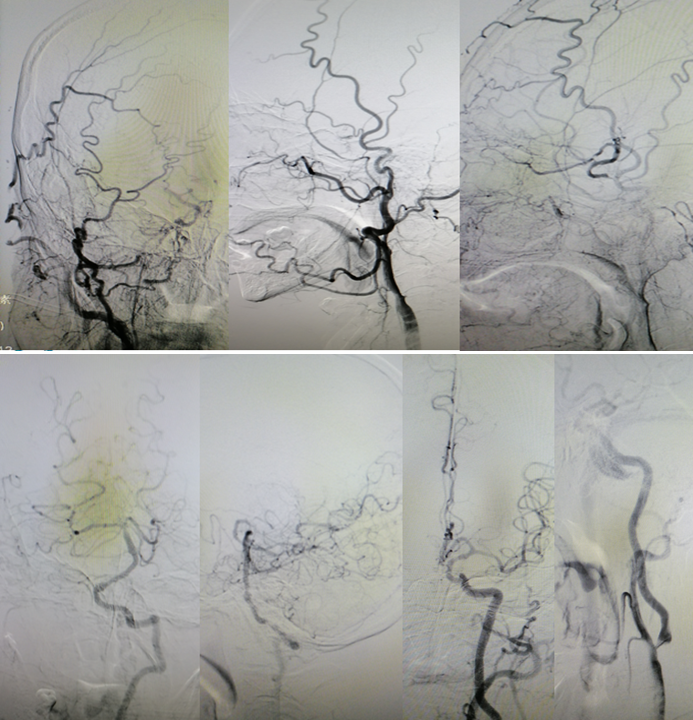

DSA

病历夹什么径技·第151期|串联营病历夹:京广连营_https://www.jmylbn.com_新闻资讯_第8张

病历夹什么径技·第151期|串联营病历夹:京广连营_https://www.jmylbn.com_新闻资讯_第9张

<<滑动查看下一张图片>>

结论:左侧颈动脉起始部位出现断流,右侧颈动脉没有明显代偿,血管形态较光滑。